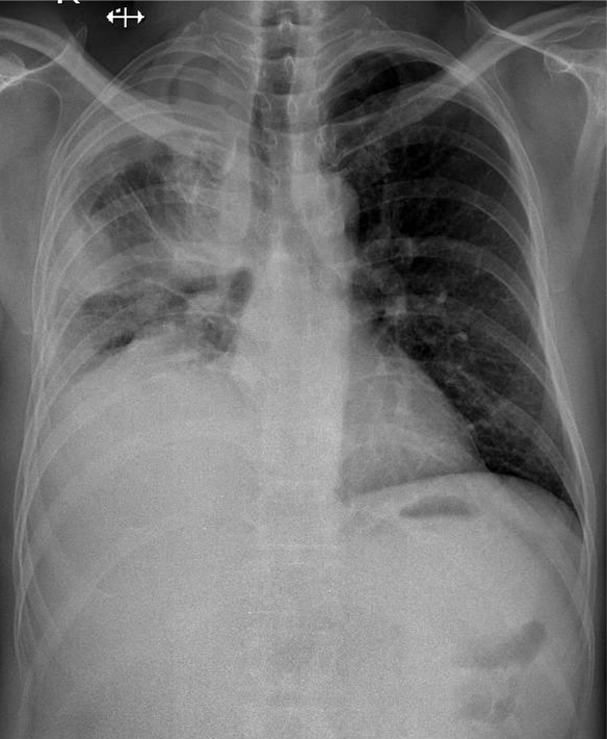

1-Thâm nhiểm phế nang lan tỏa phổi (P) => Viêm phổi 2-Tràn dịch màng phổi (P)